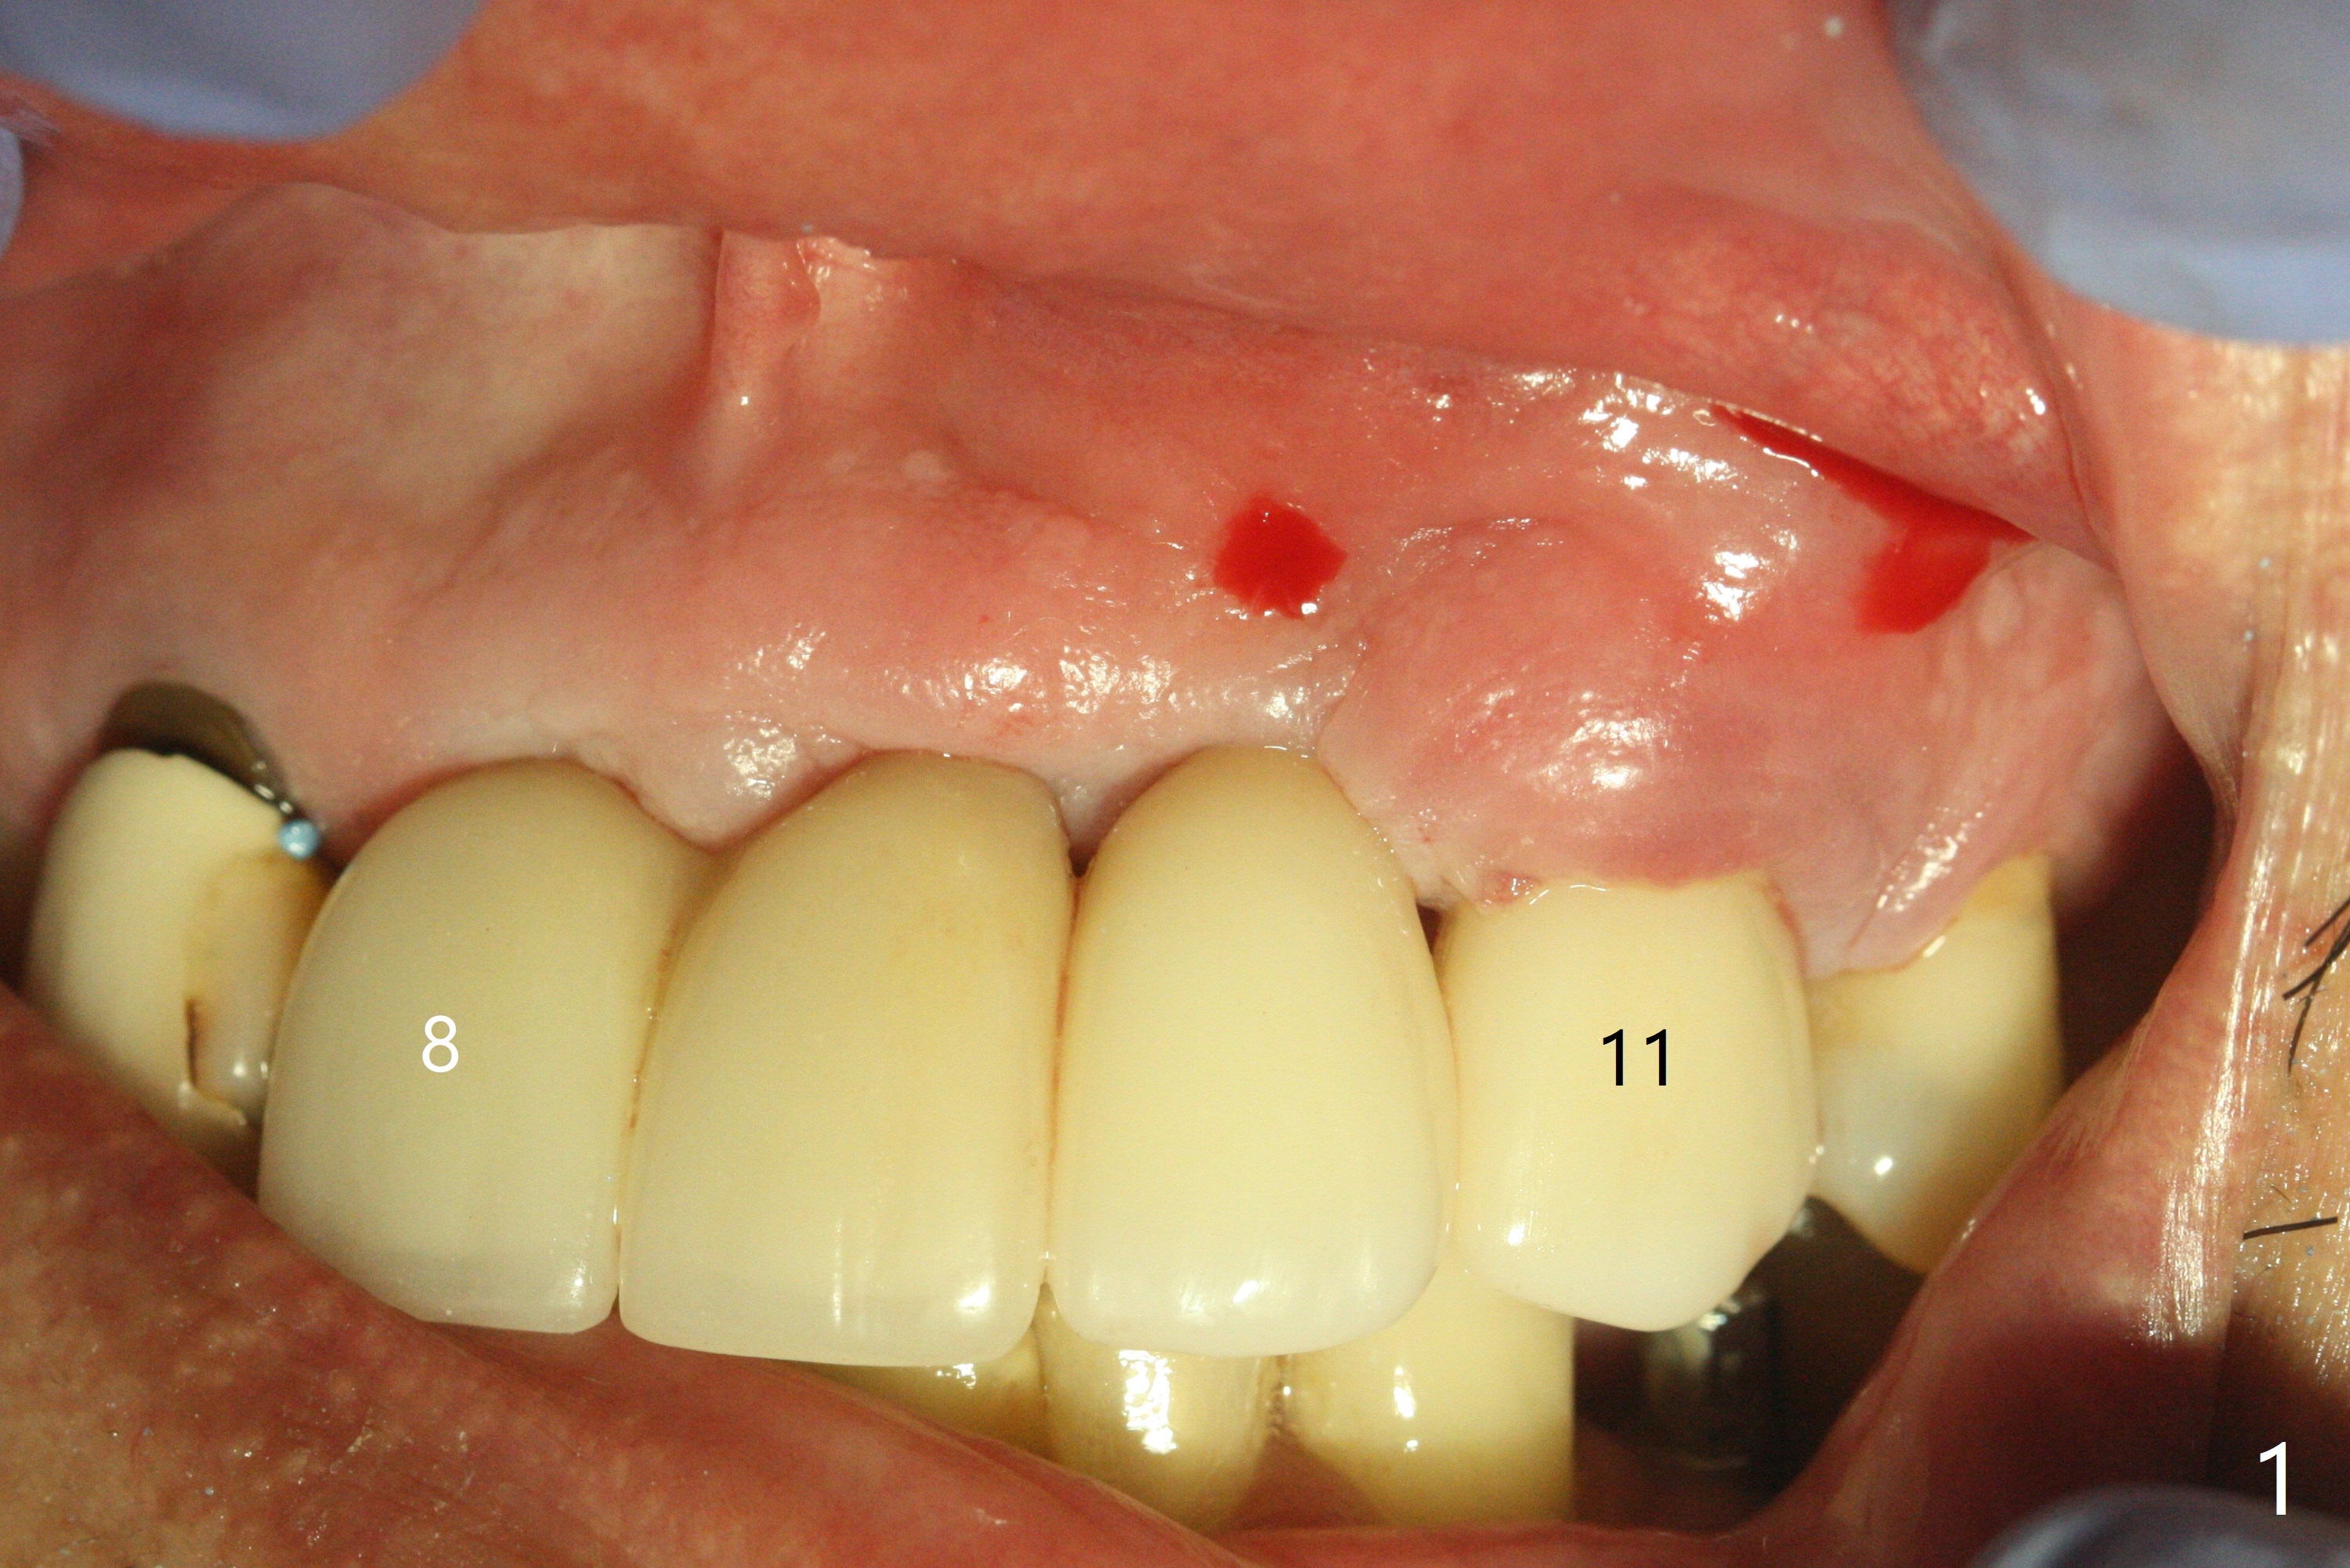

There is no obvious black triangle between the implants at #8-11 (Fig.1 post infiltration). Following papilla (Fig.2 *) sparing incision and elevation of the buccal flap, the fenetration of the buccal plate around the socket shield (Fig.3 S) is found at #11; there is a distal defect with granulation tissue (*). After shield and granulation tissue removal, the coronal implant is found exposed (Fig.4 until osteotomy). The relatively flat surface of IBS implant is apparently less likely to develop periimplantitis. With periosteal relief and placement of sticky bone (Fig.7 *), PRF and 6-month membrane, the wound is closed with 4-0 PTFE suture (Fig.5). Failure of socket shield is related to retention of the apex (Fig.6 <). Probe before extraction and remove apex and gutta percha. There appears no buccal or palatal (P) defect 9 months post shield removal (17 months post cementation, Fig.8), although the bone density palatally is low. Although the sagittal section (Fig.9 (lower left panel) shows the absent palatal plate at #10, the 3-D image and the coronal section do not (upper let and right panels). The 2.5 mm implant at #9 appears to have been placed buccal (Fig.10 B), although the buccal crest is present. In contrast the 2.5 mm implant at #8 appears within the bone boundary (Fig.11). The soft tissue remains healthy at #8-11. Bone graft will be done if needed.